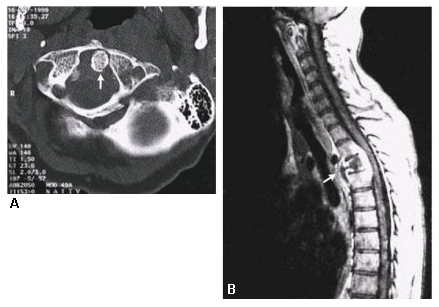

TC donde se observa TB espinal (enfermedad de Pott)

Massachusetts Medical Society; reproducido con permiso de N Engl J Med. 2002;347:1849; usado con permiso